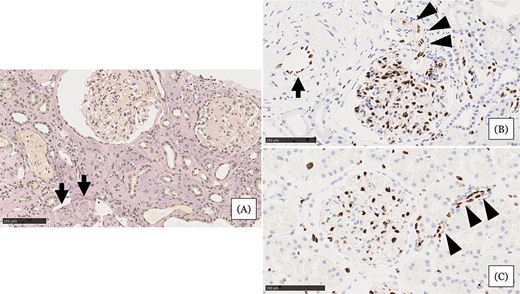

• 腎活檢示小動(dòng)脈嚴重狹窄或阻塞,內皮損害嚴重,腎小球萎縮,間質(zhì)細胞浸潤(圖1A)

• 與血壓正常的正常腎組織相比,血管內皮細胞(EC)細胞核等長(cháng)排列整齊(圖1C)

• 患者腎組織中EC細胞核大小不一,細胞核明顯,小動(dòng)脈內細胞核較少(圖1B)

綜合以上表現,診斷該患者急性腎損傷類(lèi)型為難治性高血壓合并微血管病性溶血導致的急性慢性缺血性腎損害。

圖1:住院第 31 天的腎臟活檢結果。